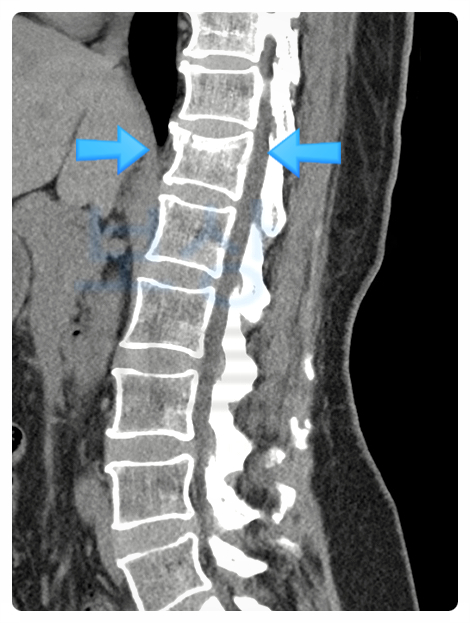

이처럼 낙상으로 인한 허리 통증이 생길 경우, 압박골절을 확진하기 위해 반드시** CT 및 MRI **촬영이 필요합니다. 또한 골밀도 검사 역시 필수로 진행됩니다. 이러한 정밀 검사 결과, 다행히 부상의 정도가 심하지 않아서 시술은 필요 없다는 소견을 받았는데요.

그 대신 TLSO 허리보조기를 8주~12주 정도 착용한 채로 자연 치유 되도록 기다려야 했습니다. 영어로는 Thoracolumbo-sacral Orthosis 의 약자이고, 정식 명칭은 흉요천부전용보장구(胸腰薦部專用補裝具)입니다. 너무 어렵죠?😊 쉽게 말해서 이 보조기는 말 그대로 허리와 척추를 보호하는 갑옷 같은 역할을 합니다.